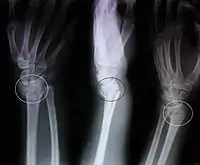

كسر كولِس (بالإنجليزية: Colles' fracture) هو كسر في النهاية البعيدة للكعبرة مع انزياح ظهري (خلفي) للمعصم واليد. يدعى هذا الكسر أحياناً بتشوه ظهر الشوكة أو تشوه الحربة بسبب الشكل الذي يأخذه مقدم الساعد. لمناقشة تفصيلية أكثر راجع كسر الكعبرة البعيد.

صورة شعاعية تظهر كسر كولس

- الميلان الظهري.

- قصر الكعبرة.

- خسارة الانحراف الزندي

- التزوي الكعبري للمعصم.

- الخلع الظهري لشدفة التفتت البعيدة في موقع الكسر

- كسر مرافق في الناتئ الإبري للزند في أكثر من 60% من الحالات.